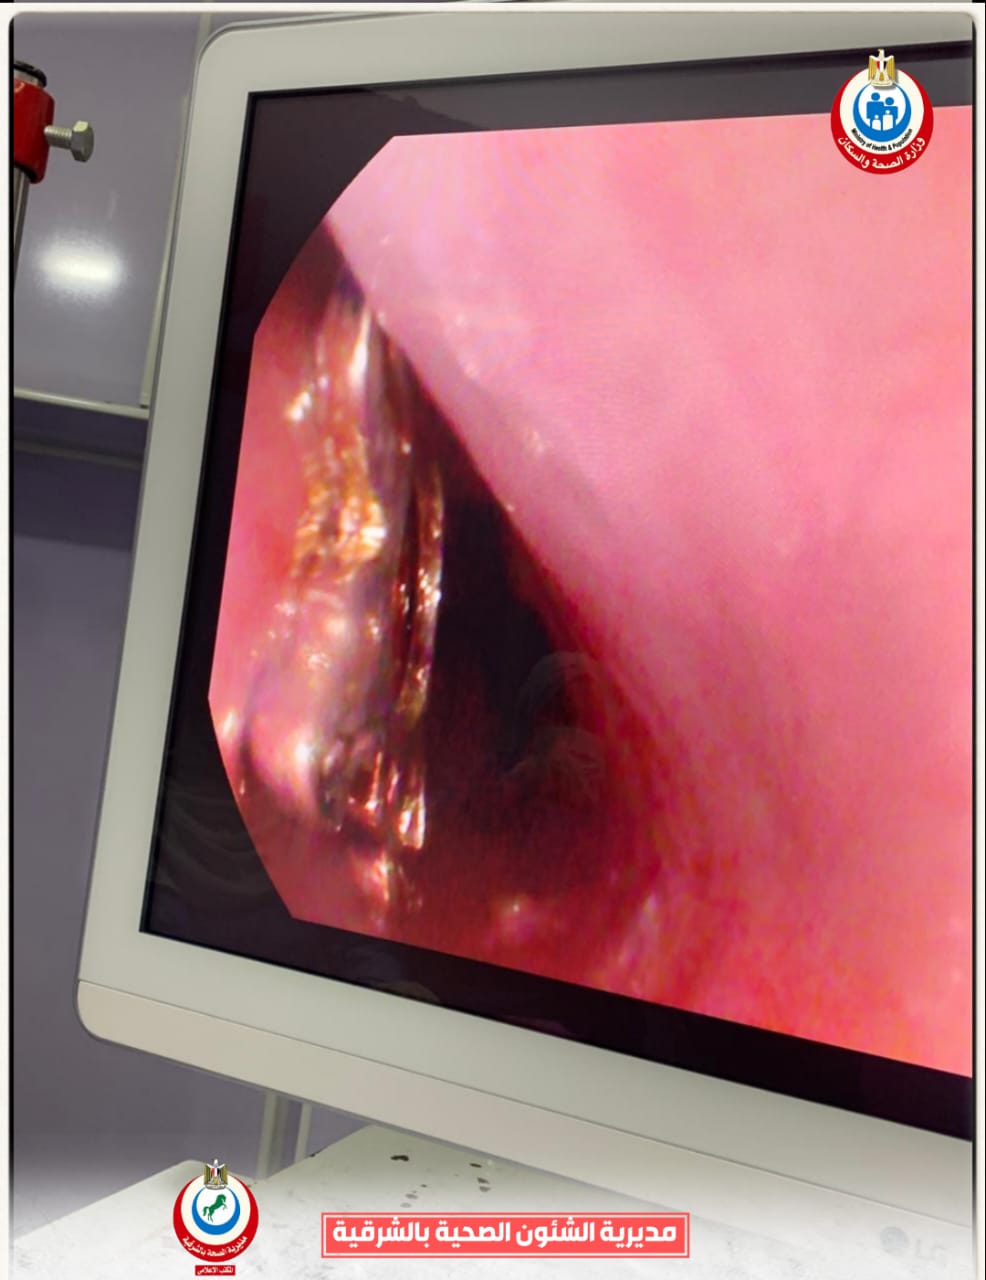

وأوضح الدكتور أحمد البيلي وكيل وزارة الصحة أن قسم المناظير بمستشفى أبو كبير شهد نجاح مميز في إنقاذ الطفلة التي تبلغ من العمر ٥ سنوات، وقامت بابتلاع سلسلة معدنية حادة ومدببة وأطرافها قادرة على إحداث جروح أو ثقوب بالزور أو داخل المعدة، وبعد استقبالها مساء أمس الثلاثاء بمستشفى مشتول السوق المركزي، وتم التنسيق السريع من خلال مركز الخدمات الطارئة ١٣٧ بالمديرية، وتحويل الحالة بسيارة الإسعاف إلى مستشفى أبو كبير في وقت قياسي، وتم التدخل العاجل بالمنظار بعد إجراء كافة الفحوصات الطبية اللازمة لها، واستخراج السلسلة من المعدة دون أي مضاعفات، وسط متابعة وتدخل فوري من الفريق الطبي بقيادة الدكتور محمد عصام خلال الفترة المسائية.

وأضاف وكيل وزارة الصحة بالشرقية بأن الفريق الطبي بقسم مناظير الكبد والجهاز الهضمي بالمستشفى، قام أيضاً بإجراء ٩ مناظير قولونية ومناظير معدة تشخيصية وعلاجية، منهم منظار لمريضة تعاني من قيء دموي حاد نتيجة نزيف من دوالي المعدة وتم حقنها بالمنظار العلاجي، كما تم استئصال زوائد لحمية متعددة بالقولون لمريض آخر يعاني من نزيف شرجي مستمر، هذا بالإضافة إلى إجراء منظار قولوني لطفل يبلغ من العمر ٤ سنوات يعاني من إمساك مزمن ونزيف شرجي، وتم أخذ عينات من قرح وزوائد بالأمعاء الدقيقة لتحليل الأنسجة.